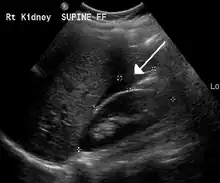

An ultrasound showing a gestational sac with fetal heart in the fallopian tube has a very high specificity of ectopic pregnancy. Transvaginal ultrasonography has a sensitivity of at least 90% for ectopic pregnancy.[4] The diagnostic ultrasonographic finding in ectopic pregnancy is an adnexal mass that moves separately from the ovary. In around 60% of cases, it is an inhomogeneous or a noncystic adnexal mass sometimes known as the "blob sign". It is generally spherical, but a more tubular appearance may be seen in case of hematosalpinx. This sign has been estimated to have a sensitivity of 84% and specificity of 99% in diagnosing ectopic pregnancy.[4] In the study estimating these values, the blob sign had a positive predictive value of 96% and a negative predictive value of 95%.[4] The visualization of an empty extrauterine gestational sac is sometimes known as the "bagel sign", and is present in around 20% of cases.[4] In another 20% of cases, there is visualization of a gestational sac containing a yolk sac or an embryo.[4] Ectopic pregnancies where there is visualization of cardiac activity are sometimes termed "viable ectopic".[4]

Transvaginal ultrasonography of an ectopic pregnancy, showing the field of view in the following image.

A small amount of anechogenic-free fluid in the recto-uterine pouch is commonly found in both intrauterine and ectopic pregnancies.[4] The presence of echogenic fluid is estimated at between 28 and 56% of women with an ectopic pregnancy, and strongly indicates the presence of hemoperitoneum.[4] However, it does not necessarily result from tubal rupture but is commonly a result from leakage from the distal tubal opening.[4] As a rule of thumb, the finding of free fluid is significant if it reaches the fundus or is present in the vesico-uterine pouch.[4] A further marker of serious intra-abdominal bleeding is the presence of fluid in the hepatorenal recess of the subhepatic space.[4]